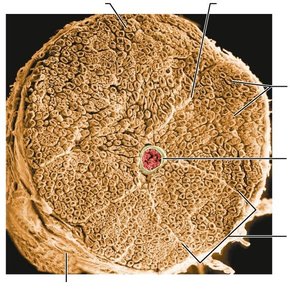

Structure of a Nerve

Nerves are cordlike organs of the PNS, consisting of bundles of myelinated and nonmyelinated axons enclosed by connective tissue layers:

Endoneurium: Surrounds individual axons.

Perineurium: Bundles groups of axons into fascicles.

Epineurium: Encloses all fascicles to form the nerve.